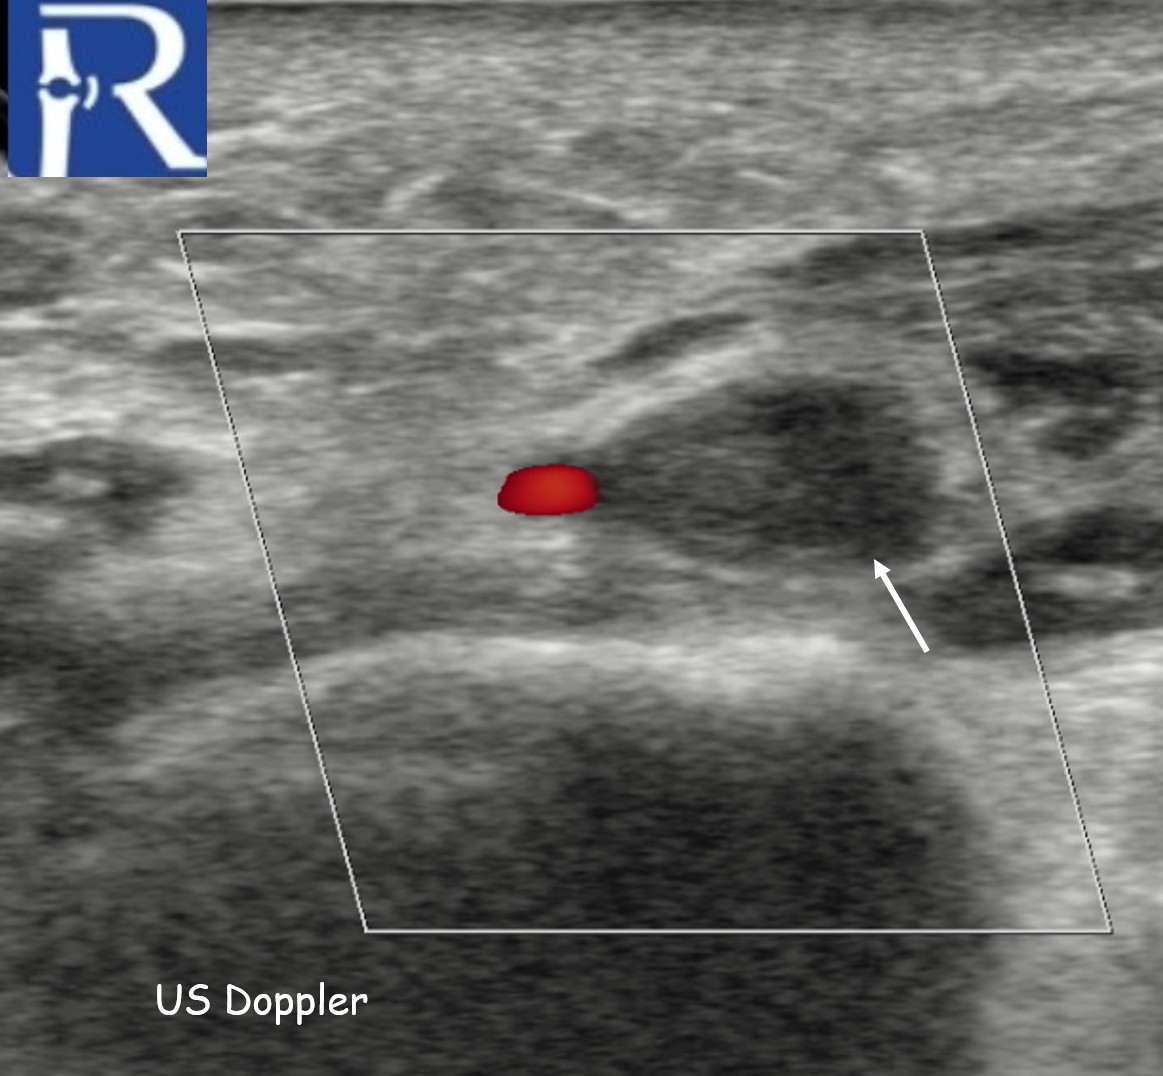

The case was initially reported as negative for venous thrombosis on routine Doppler examination. However, when reassessment was specifically requested with attention to the plantar venous system, duplex ultrasound confirmed lateral plantar vein thrombosis

A critical issue appears to be protocol-related: plantar veins are not routinely included in standard lower extremity DVT ultrasound examinations. As a consequence, thrombosis confined to these distal venous structures may go undetected unless specifically targeted.

Targeted inclusion of the medial and lateral plantar veins in duplex ultrasound evaluation may be appropriate.